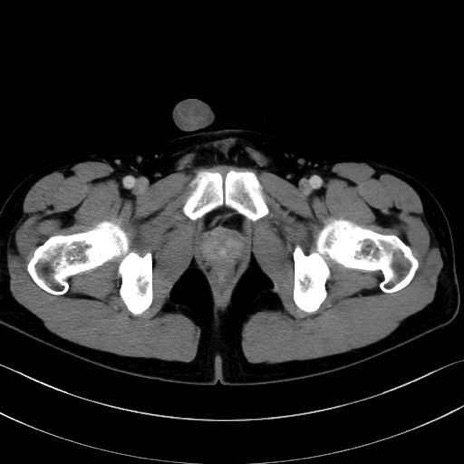

小殿筋 (Gluteus minimus)